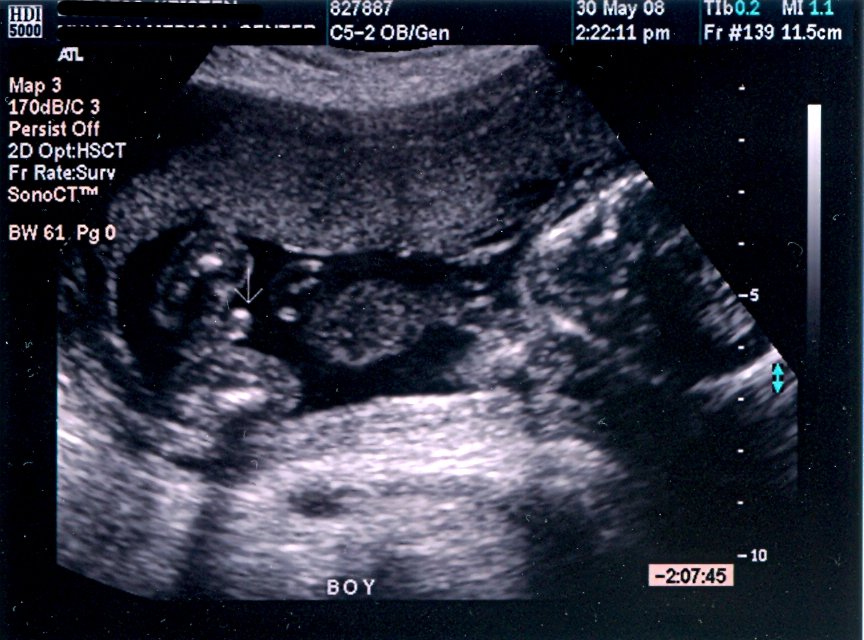

soo....all has been revealed today regarding whether there are 1 or 2 in there and yep there is only 1...and for the first time in 5 pregnancies....a normal size one......

i had my glucose tollerance test today and whilst there spoke to the midwife about my concerns that i couldn't feel the baby move at all yet and that i keep hearing 2 heartbeats...well....i thought she will do a doppler and then examine me but instead i got a bonus ulteasound..yeah....i saw my peanut today.....i cannot claim i could tell what it was because my focus was if the baby was alive and kicking......and i didn't want change the topic from genuine viability worry to mere gender concern to the midwife so kept looking at the image for heartbeat and movement although gazing at the important parts too form time to time...;)...i have to admit i didn't see any 'real' gender clues.....neither boy or girl...although assumed i saw alot of lines now and again...but maybe that is what i wanted to see so it could be in my head... ???? hence, i canot truly claim i know what i think it may because it may be too good to be true.....and no point getting ahead of myself...since nothing is really confirmed.....20 week scan in 2 weeks time but no intention to find out......i think....

any skull or nub ideas most welcome!!!!!!!!!!!!!!!!